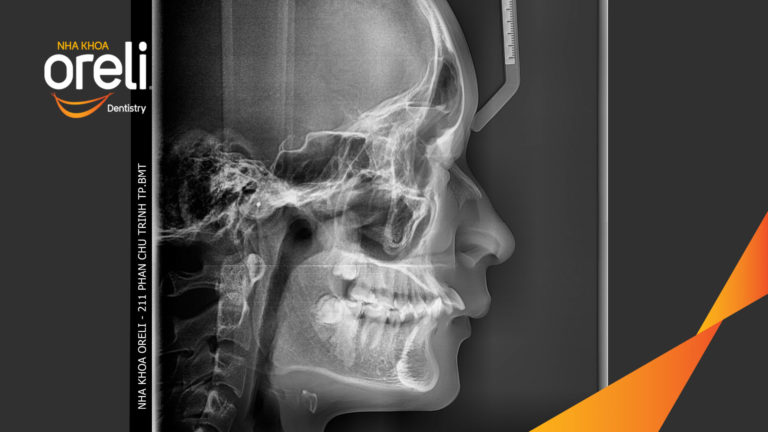

Niềng răng hô nặng phải nhổ 4 răng số 4 cho góc nghiêng và hàm răng đều đẹp – Hành trình tại Oreli Niềng răngHô Xem thêm